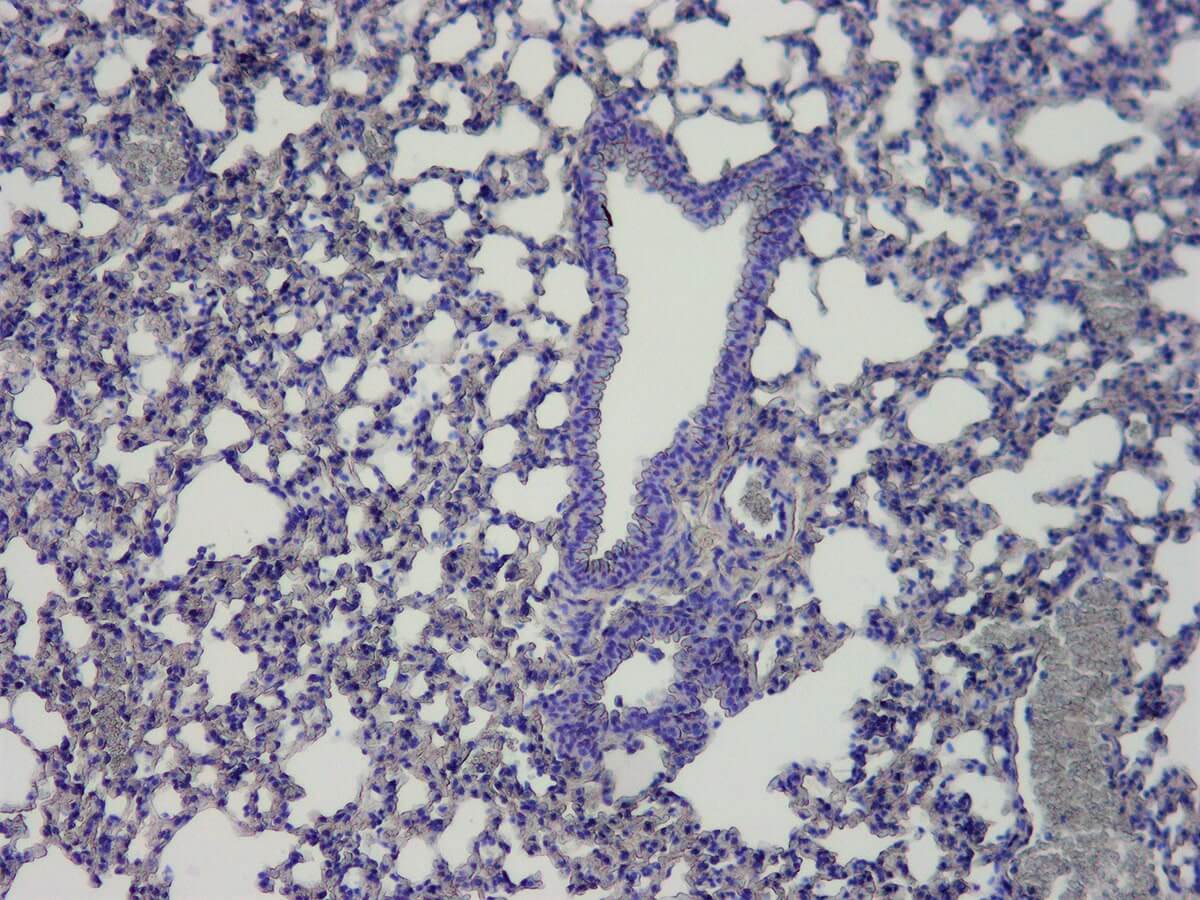

Hematoxylin is frequently used together with Eosin, nuclear fast red, periodic acid or alcian blue. It is also used in immunohistochemical procedures to visualize the end product. This product does not contain mercury.

KH07003-Harris-H-Lung-10-x.jpg     KH07003-Harris-H-Liver-10-x.jpg

Nuclei can be visualized as blue-purple.